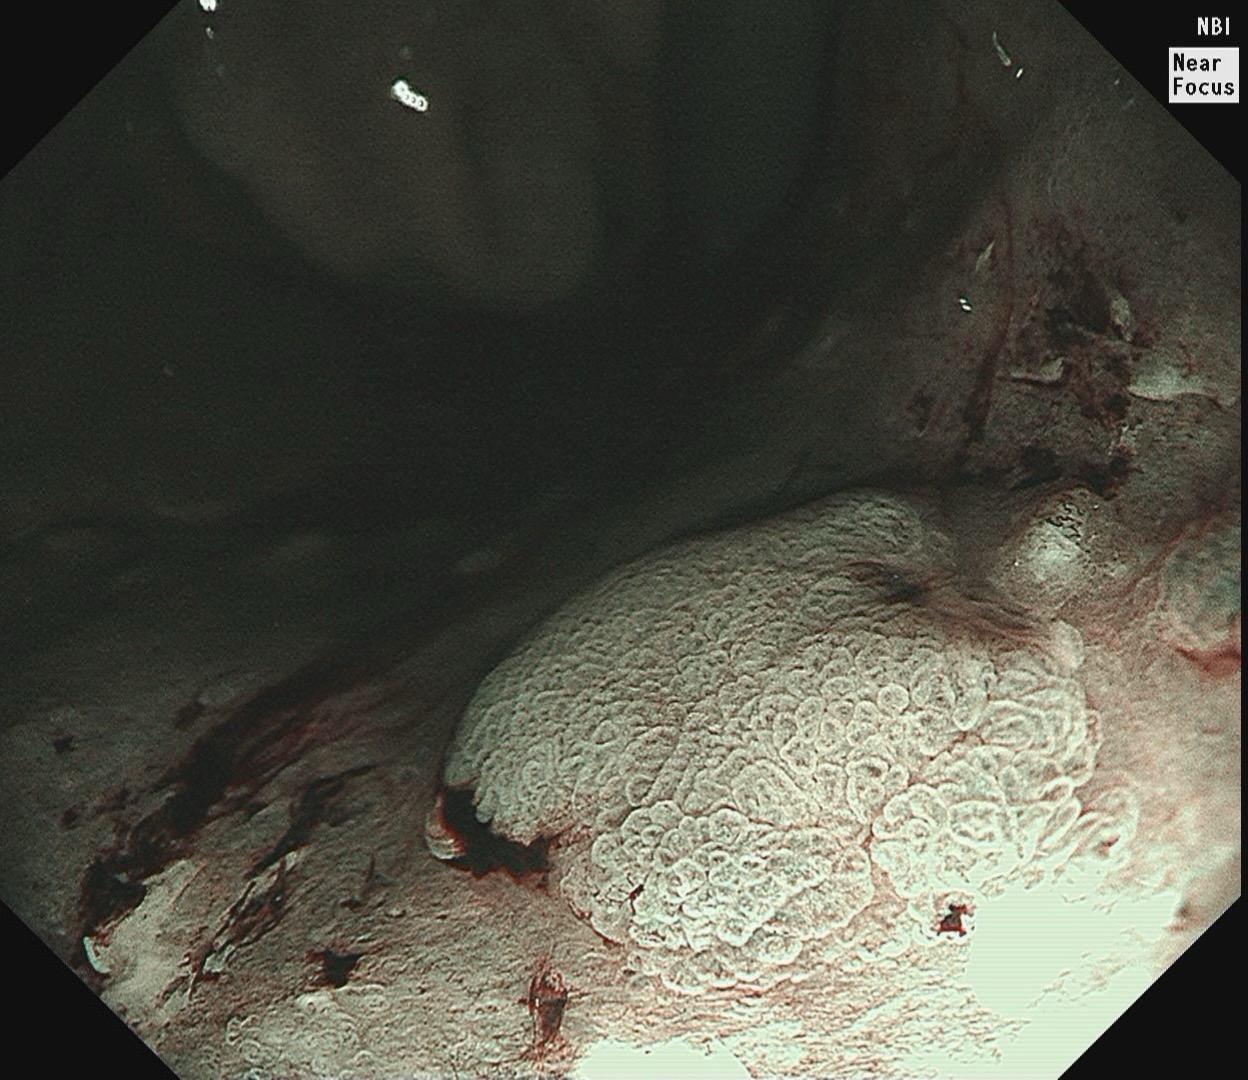

男,61岁,胃巨大褪色调病变。答案在最后一张图片,你猜对了吗? 患者因上腹部饱胀行胃镜检查,Hp阴性背景,胃窦至贲门下见一巨大褪色调病变,边界清晰,病变相对表浅,未见明显溃疡及隆起,胃壁较柔软,充气顺应性佳,予多点活检确诊,拟外科手术行全胃切除。做这么多年胃镜,还是第一次遇到这样的……